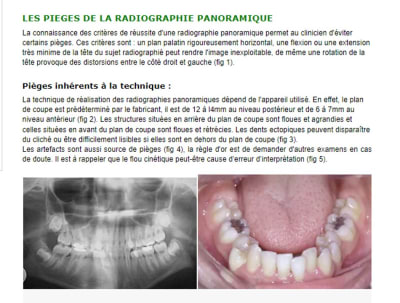

En résumé tu donnes des leçons et tu te fais piégé dans l'analyse d'une pano

Extrait d'un article sur le sujet :

"

Pièges inhérents à la technique :

La technique de réalisation des radiographies panoramiques dépend de l'appareil utilisé. En effet, le plan de coupe est prédéterminé par le fabricant, il est de 12 à l4mm au niveau postérieur et de 6 à 7mm au niveau antérieur (fig 2). Les structures situées en arrière du plan de coupe sont floues et agrandies et celles situées en avant du plan de coupe sont floues et rétrécies. Les dents ectopiques peuvent disparaître du cliché ou être difficilement lisibles si elles sont en dehors du plan de coupe (fig 3).

Les artefacts sont aussi source de pièges (fig 4), la règle d'or est de demander d'autres examens en cas de doute. Il est à rappeler que le flou cinétique peut-être cause d’erreur d’interprétation (fig 5).

"

> En résumé tu donnes des leçons et tu te fais piégé dans l'analyse d'une pano

oui un cas bien iconographié... les photos bien prises pour qu on ne voit pas les parties intéressantes... les radios qui illustrent mais pareil faut pas trop les regarder... et surtout faire confiance a posit parce que entre ce que tu dis et l iconographie y a rien qui correspond ;)